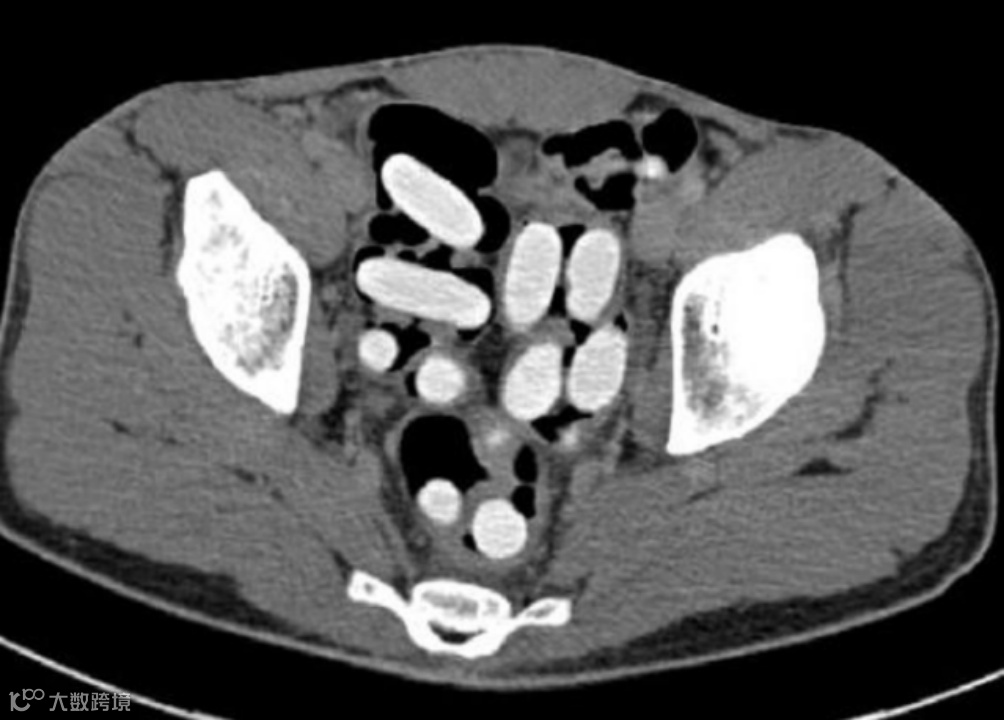

作为普通的放射科医生或技师,我们也可以在反诈、禁毒中尽自己的绵薄之力,尤其是看到这样图像时,请立即报警❗️❗️❗️

腹部CT扫描显示结肠(主要是降结肠、乙状结肠和直肠)有大量椭圆形高密度异物,这可不是“可爱的蚕宝宝”,而是小包分包的可卡因,大约有300-500g。